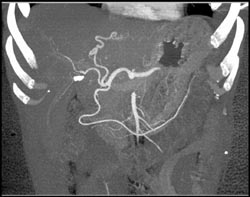

Cholangiocarcinoma